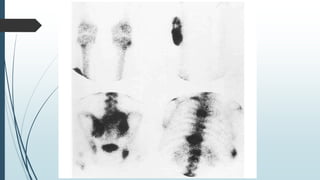

Radionuclide scan

Increased vascularity in blood pool phase.

Hard mass in middle-aged man’s calf for 8 years

T1 Contrast + shows Extraskeletal Mesenchymal Chondrosarcoma